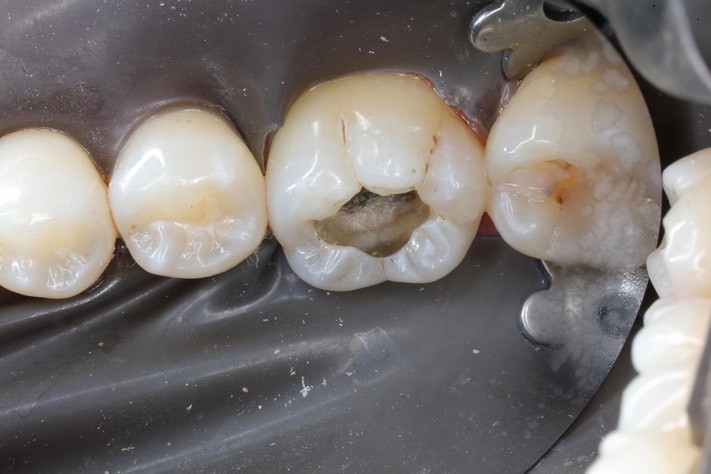

Kris Nip #19 caries removal